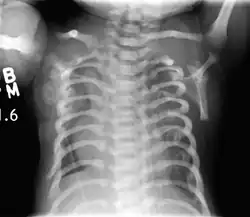

| CXR of a newborn with asphyxiating thoracic dysplasia. Note the short ribs. | |

Jeune syndrome is a rare autosomal recessive ciliopathy.[7] This diagnosis is grouped with other chest problems called thoracic insufficiency syndrome (TIS). Diagnosis of Jeune syndrome can be made as early as before birth if signs and symptoms are apparent on an ultrasound; however, diagnosis after birth usually occurs through X-rays and genetic testing, such as the tests found on the Genetic Testing Registry (GTR).[8]